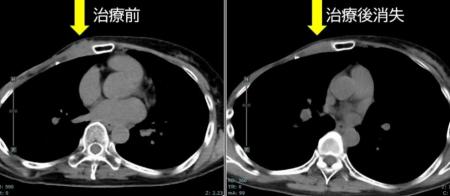

・FDG-PET陽性の浅在性腫瘍に対するBNCT(jRCTs031240204)治療4例目:再発乳がん

治療前約37mmの腫瘍が、治療3カ月後の画像診断で消失しています。

また、もともと基準値内(25以下)だった腫瘍マーカー(CA15-3)は20.9から10.7まで低下しています。

[画像1:

https://prcdn.freetls.fastly.net/release_image/173238/1/173238-1-1a6e6db7f9854eaa8057316d4354f51f-893x389.jpg?width=536&quality=85%2C75&format=jpeg&auto=webp&fit=bounds&bg-color=fff ]